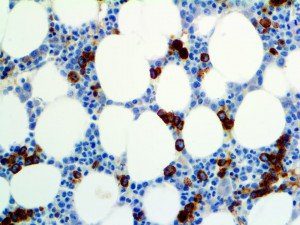

It is the ICU physician who is most likely to witness one of the deadliest manifestations of the abnormal immunological response, the cytokine storm syndrome (CSS). This response is also referred to by some as the cytokine release syndrome (CRS). CSS is characterized by continuous activation and expansion of macrophage and lymphocyte populations, which secrete large amounts of cytokines, causing the cytokine storm. This massive cytokine release is akin to hemophagocytic lymphohistiocytosis (HLH) disease, a syndrome characterized by initial unchecked and persistent activation of cytotoxic T lymphocytes and NK cells.

Clinical and laboratory manifestations of HLH include fever, enlarged liver and/or spleen, neurologic dysfunction, coagulopathy, liver dysfunction, cytopenias (i.e., low levels of erythrocytes, leukocytes, and/or platelets), hypertriglyceridemia, hyperferritinemia, hemophagocytosis, and eventually diminished NK cell activity as the immune system becomes progressively paralyzed. HLH can be familial (primary HLH) or secondary to another disease process (sHLH), such as rheumatic disease, in which it is referred to as macrophage activation syndrome (MAS, characterized by elevated ferritin).